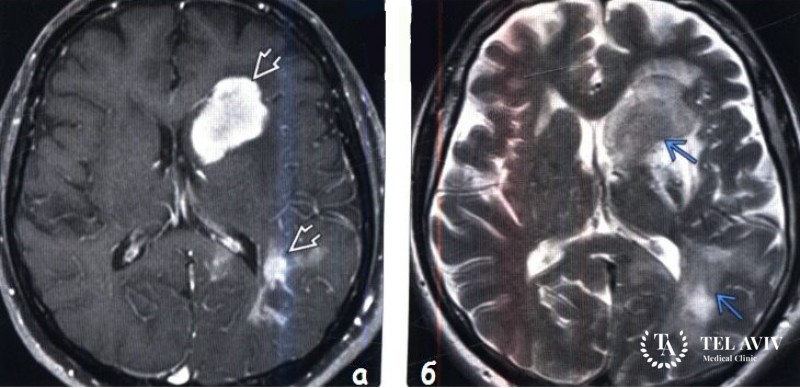

- МРТ или КТ;